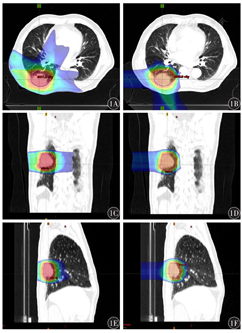

所有计划均能满足处方剂量覆盖95%的靶区体积照射。相对于IMRT,IMPT的低剂量范围减小,剂量集中于靶区附近(图1)。根据DVH图,IMPT和IMRT PTV靶区的CI、HI、V95%和V100%差异均无统计学意义(均P>0.05)(表1)。